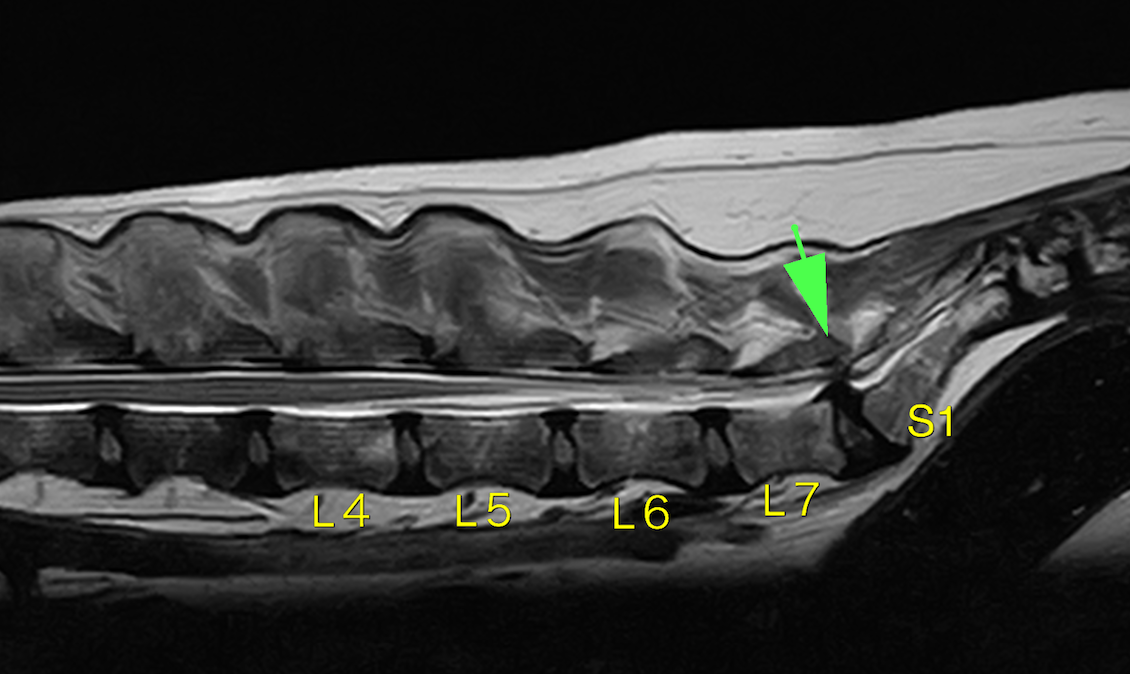

L7とS1(第7腰椎と仙骨)の部分での神経圧迫が確認できました。

L7-S1の間に圧迫が見られます。